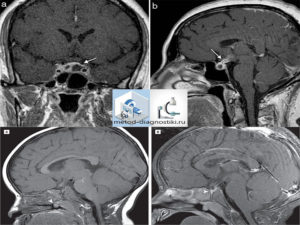

- Опухоли. Аденома является наиболее частой находкой МРТ. Ее размеры бывают до 10 мм, тогда ее называют микроаденомой. Если новообразование имеет диаметр от 1 см до 2,2см, но не распространяется за пределы турецкого седла, то ее относят к мезоаденомам. Макроаденомы имеют в поперечнике более 2,5 см. Если опухоль не обнаружена, но имеются косвенные признаки ее наличия, то устанавливают предварительный диагноз, который потом уточняют при операции. При обнаружении просветлений в ткани, имеющих размеры от 1 до 3 мм, их наличие, расценивается, как аденопатия. Под таким диагнозом понимают обратимые изменения, которые без лечения или на фоне гормональной терапии исчезают.

При применении контраста мелкие аденомы его накапливают медленнее, что приводит к стиранию разницы между ними и окружающим гипофизом. Поэтому иногда приходится уже во время проведения МРТ вводить дополнительное количество препарата для четкой визуализации.

Аденома является наиболее частой находкой МРТ. Ее размеры бывают до 10 мм, тогда ее называют микроаденомой.

Если новообразование имеет диаметр от 1 см до 2,2 см, но не распространяется за пределы турецкого седла, то ее относят к мезоаденомам. Макроаденомы имеют в поперечнике более 2,5 см.

При выходе из полости турецкого седла аденома прорастает в соседние ткани, синусы и желудочки мозга, цистерну, носовые ходы.

Если опухоль не обнаружена, но имеются косвенные признаки ее наличия на фоне клинических проявлений и гормональных нарушений, то устанавливают предварительный диагноз, который потом уточняют при операции. К таким симптомам относятся:

- неоднородная структура, очаги повышенной или пониженной плотности;

- выраженная асимметрия и смещение воронки гипофиза;

- деформация костей турецкого седла, разрушение спинки, остеопороз.

При обнаружении просветлений в ткани, имеющих размеры от 1 до 3 мм их наличие, расценивается, как аденопатия. Под таким диагнозом понимают обратимые изменения, которые без лечения или на фоне гормональной терапии исчезают. Для того, чтобы не пропустить подобные нарушения важно проводить исследование на высокоточных томографах с толщиной среза 2-3 мм.

При применении контраста мелкие аденомы его накапливают медленнее, что приводит к стиранию разницы между ними и окружающим гипофизом. Поэтому иногда приходится уже во время проведения МРТ вводить дополнительное количество препарата для более четкой визуализации.